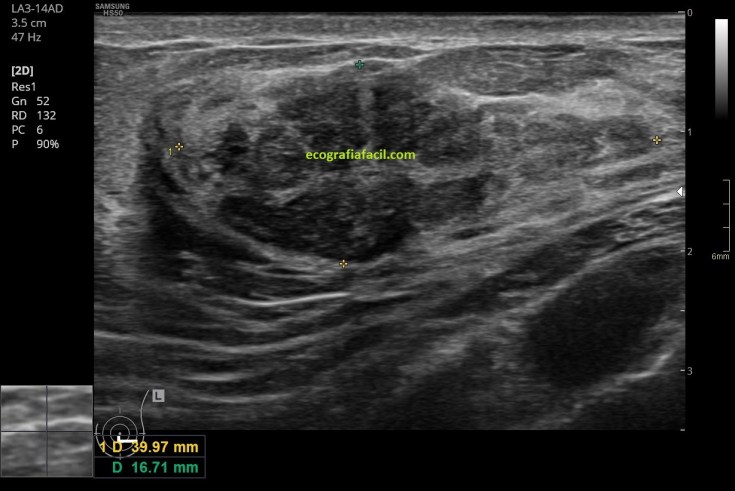

La masa en cuestión no tiene unos bordes excesivamente nítidos (imagen 2), pero por su volumen fue fácil de capturar y si lo observas detalladamente sus bordes son lo bastante visibles para poder ver la lesión y estudiarla.

Internamente es, como he dicho, heterogénea (la paleta solo tiene grises, pero en la lesión son muchos y están muy mezclados), como puedes ver en la imagen 2, 3, 5 y 5, la vascularización, imagen 6, en este caso era muy escasa o nula. No hay alteración de los tejidos colindantes de la lesión y ésta, transmite bien.

En la imagen 4 y 5 el estudio estándar, cortes axiales y longitudinales de la lesión.